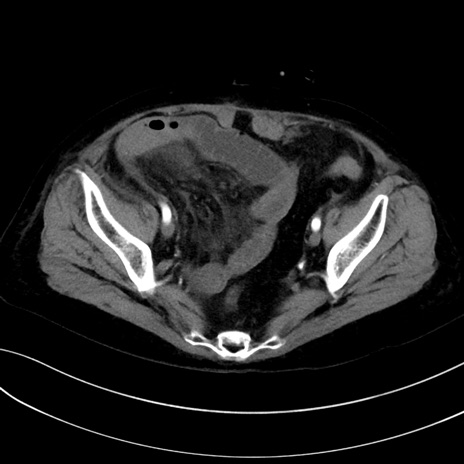

症例13 CT(横断像)1日半後